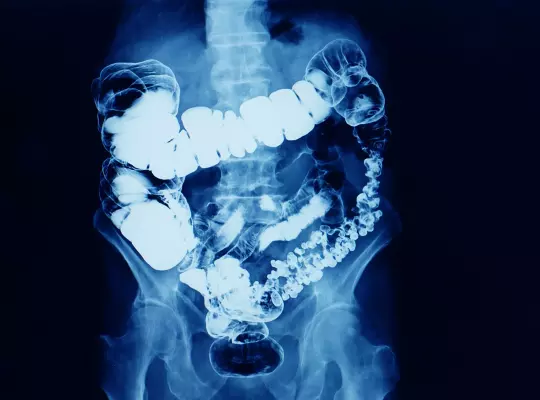

RTG, które wymagają szczególnego przygotowania:

- RTG kręgosłupa lędźwiowo-krzyżowego AP i bok

- RTG kręgosłupa lędźwiowo-krzyżowego w projekcji AP

- RTG kręgosłupa lędźwiowo-krzyżowego w projekcji bocznej

- RTG stawów krzyżowo-biodrowych

- RTG przeglądowe jamy brzusznej

- RTG kości krzyżowej

- RTG kości ogonowej

Jeżeli twoje badanie znajduje się na liście, pamiętaj!

Dzień przed badaniem:

- dieta lekkostrawna z wyłączeniem jarzyn, owoców, ciemnego pieczywa

- nie pić napojów gazowanych

- przyjąć Espumisan 3 razy dziennie po 2 kapsułki

W dniu badania:

- należy zadbać o wypróżnienie,

- nie należy palić papierosów ani żuć gumy,